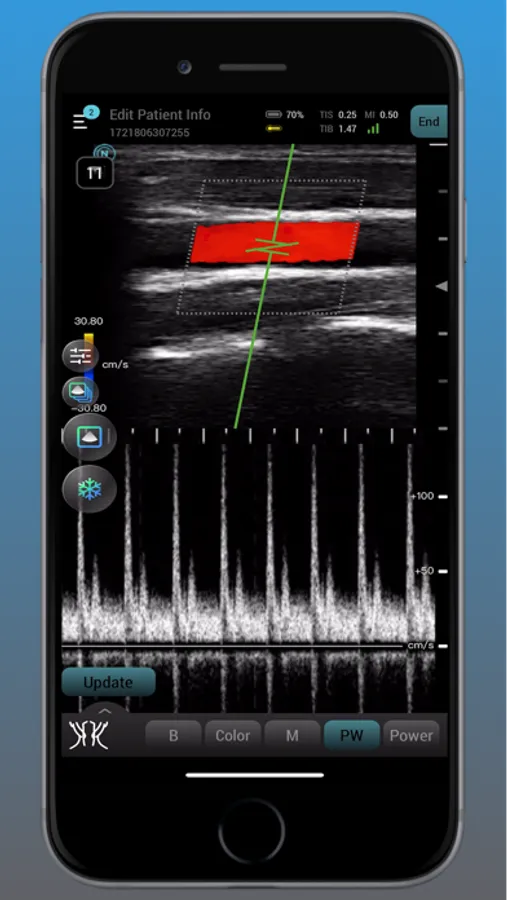

Neo Medical Ultrasound offers high imaging quality in real-time for physicians to improve daily patience care. Neo Medical app features different modes such as B Mode, Color Doppler, Pulsed Wave, and Motion mode. It is designed for medical professionals to easily access user interface to enhance portability and efficiency in daily workflows.

neo Medical Ultrasound System Screenshots